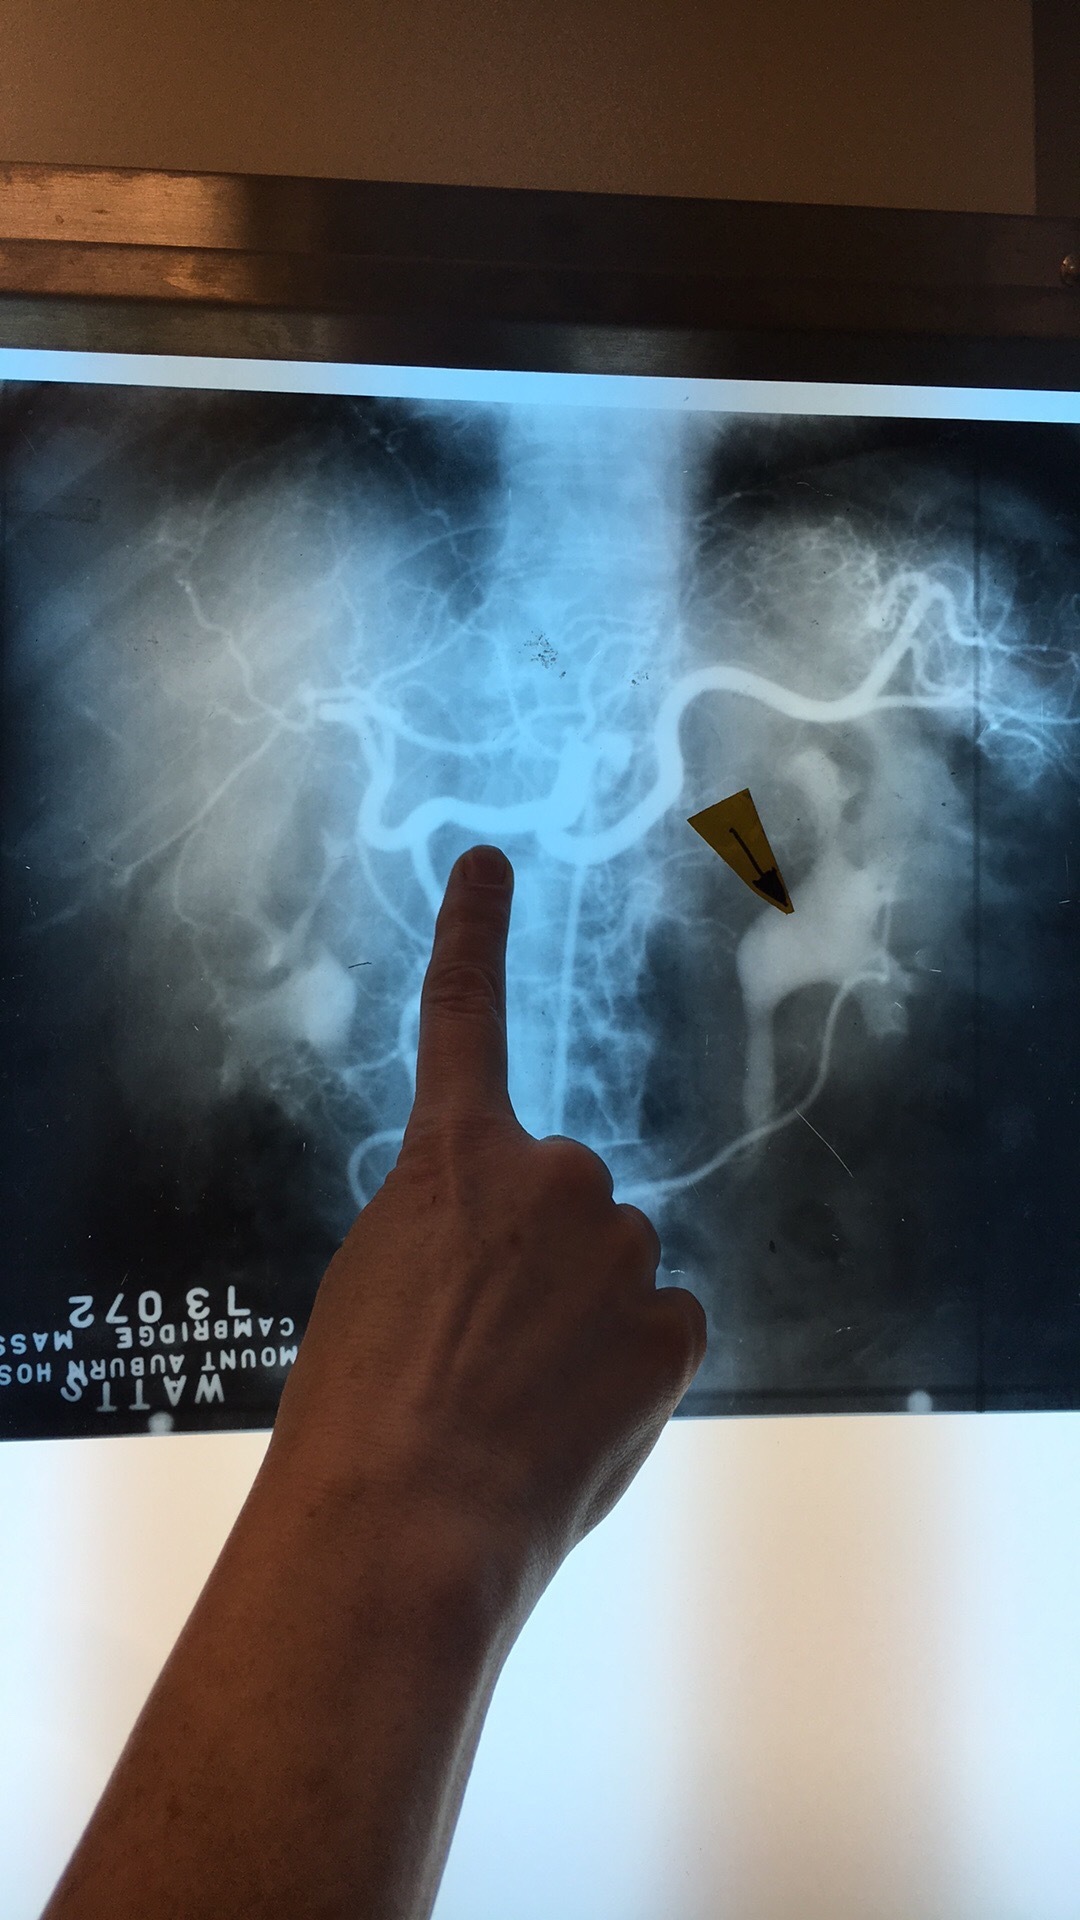

What artery? What comes off it?

Celiac Trunk. Left Gastric Art, Splenic Artery, Common Hepatic Artery